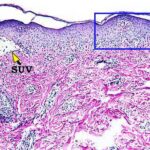

Histopathology. EM is considered the prototype of the vacuolar form of interface dermatitis . The early changes include vacuolization of the basal cell layer; tagging of lymphocytes along the dermal-epidermal junction; and a sparse, superficial, perivascular lymphoid infiltrate . Necrosis of individual keratinocytes in the basal unit occurs, which is the hallmark of EM. Because of its acute nature, there is an orthokeratotic stratum corneum. Mild spongiosis, papillary dermal edema, and extravasation of red blood cells are seen. As the lesion becomes more developed, there is a moderate lichenoid infiltrate of Iymphohistiocytes at the dermal-epidermal junction with exocytosis. More apoptotic keratinocytes within and above the basal epidermal layer are present. The |

intensity of epidermal necrosis varies from vacuolated individual keratinocytes surrounded by lymphocytes (satellite cell necrosis) at the basal unit to confluent necrosis in association with intraepidermal and subepidermal vesicles. The dermal infiltrate comprises lymphocytes and histiocytes. Eosinophils may also be present. Although one study has noted a significant number of eosinophils in drug-induced EM, this has not been noted by others. In the authors’ estimation, a generous number of eosinophils exclude EM. One study has found that an acrosyringium concentration of apoptotic keratinocytes in EM is a clue to a drug etiology . In early lesions of SJSITEN, apoptotic keratinocytes are observed scattered in the basal layer of the epidermis. In established lesions, there are numerous necrotic keratinocytes, even full-thickness epidermal necrosis, and a subepidermal bulla. The dermal inflammatory infiltrate is sparser in TEN than in EM (Fig. 9-278). Extravasated erythrocytes are commonly found within the blister cavity. Melanophages within the papillary dermis occur in late lesions. Eccrine epithelium shows a variety of changes from basal cell apoptosis to necrosis of the duct. |

In general, EM shows less epidermal necrosis, more dermal inflammation, and exocytosis, whereas SJS and TEN reveal more epidermal necrosis, less dermal inflammation, and exocytosis. However, due to the overlapping histologic features among EM, SJS, and TEN, histologic examination-while important for recognizing the spectrum of disorders-is not reliable for classifying the disease. Correlation with clinical presentation is essential. |